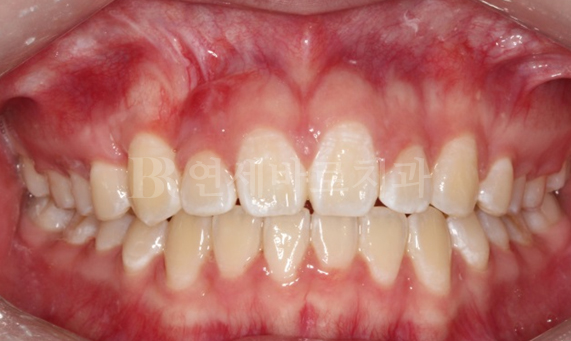

부분교정 CASE

연세바로치과 교정의 특별함

-